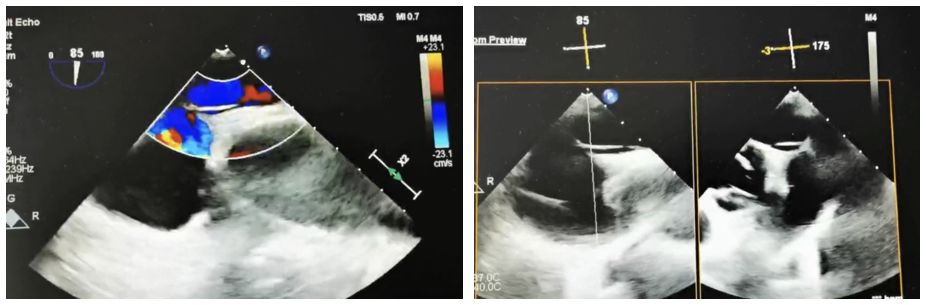

Case Information: A 60-year-old male patient was admitted to the neurology department after experiencing "left-sided limb weakness". The patient underwent a routine transesophageal echocardiogram (TEE), which revealed a patent foramen ovale (PFO) (congenital type, 2.4mm in width, 33mm in length, with moderate shunting). Right heart echocardiography and bubble tests confirmed a grade II shunt.

Estratégia Clínica: Escolhemos o oclusor simétrico BDPFO-I 2828 para garantir o fechamento ideal. Durante a fase da liberação, a imagem lactente de DSA foi usada posicionando, quando a orientação do ultrassom foi empregada primeiramente para assegurar a aplicação exata.